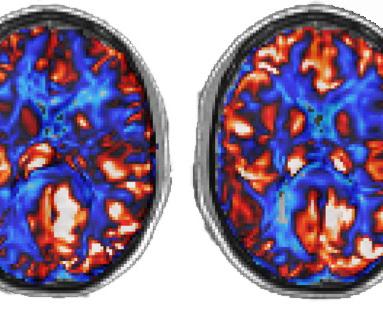

Regional and global gains in cerebral blood flow were accompanied by increased white matter integrity, which is the wiring of the brain that allows information to travel between brain cells, and increased speed of neural response across important brain networks, a function that allows thoughts and words to flow freely.

Approximately 25% of those deployed during the first Persian Gulf War, more than 250,000 veterans, have been diagnosed with Gulf War Illness (GWI). Although medical professionals have acknowledged the potentially disabling illness for nearly two decades, the neurological basis of GWI has been largely elusive. Novel findings from a study recently published in Clinical Psychological Science by Center for BrainHealth researchers Dr. Bart Rypma and Nick Hubbard, along with nationally recognized GWI expert Robert W. Haley, M.D. of UT Southwestern Medical Center, positively confirm deficits in working memory and reveal a neurobiological marker unique to the illness. Compared to matched controls, study participants with GWI demonstrated diminished capacity in three components of working memory: accuracy, speed, and efficiency. Consistent with these memory changes, brain imaging in participants with GWI revealed a distinct biomarker that could serve as a way to diagnose the disease and provide an accurate measure for treatment efficacy. These findings may hold implications for other disorders that give rise to cognitive impairment, including Alzheimer’s disease.

Three times a week for 12 consecutive weeks participants were required to complete supervised, one-hour stationary bike or treadmill workouts. Six weeks into the exercise regimen, non-invasive brain imaging techniques revealed increased brain blood flow and allowed researchers to predict significant memory gains before they were documented on cognitive tests. “There are two key findings in the current study,” said Sina Aslan, Ph.D., founder and president of Advance MRI and collaborator on the study. “First, the anterior cingulate, which has been linked to superior cognition late in life, showed higher blood flow and second, the hippocampus blood flow increase, which may prevent Alzheimer’s disease, predicted memory gains. ” Although the ability of aerobic activity to quickly enhance memory and potentially stave-off Alzheimer’s disease is impressive, changing the way you think offers far more robust brain gains. In another recent